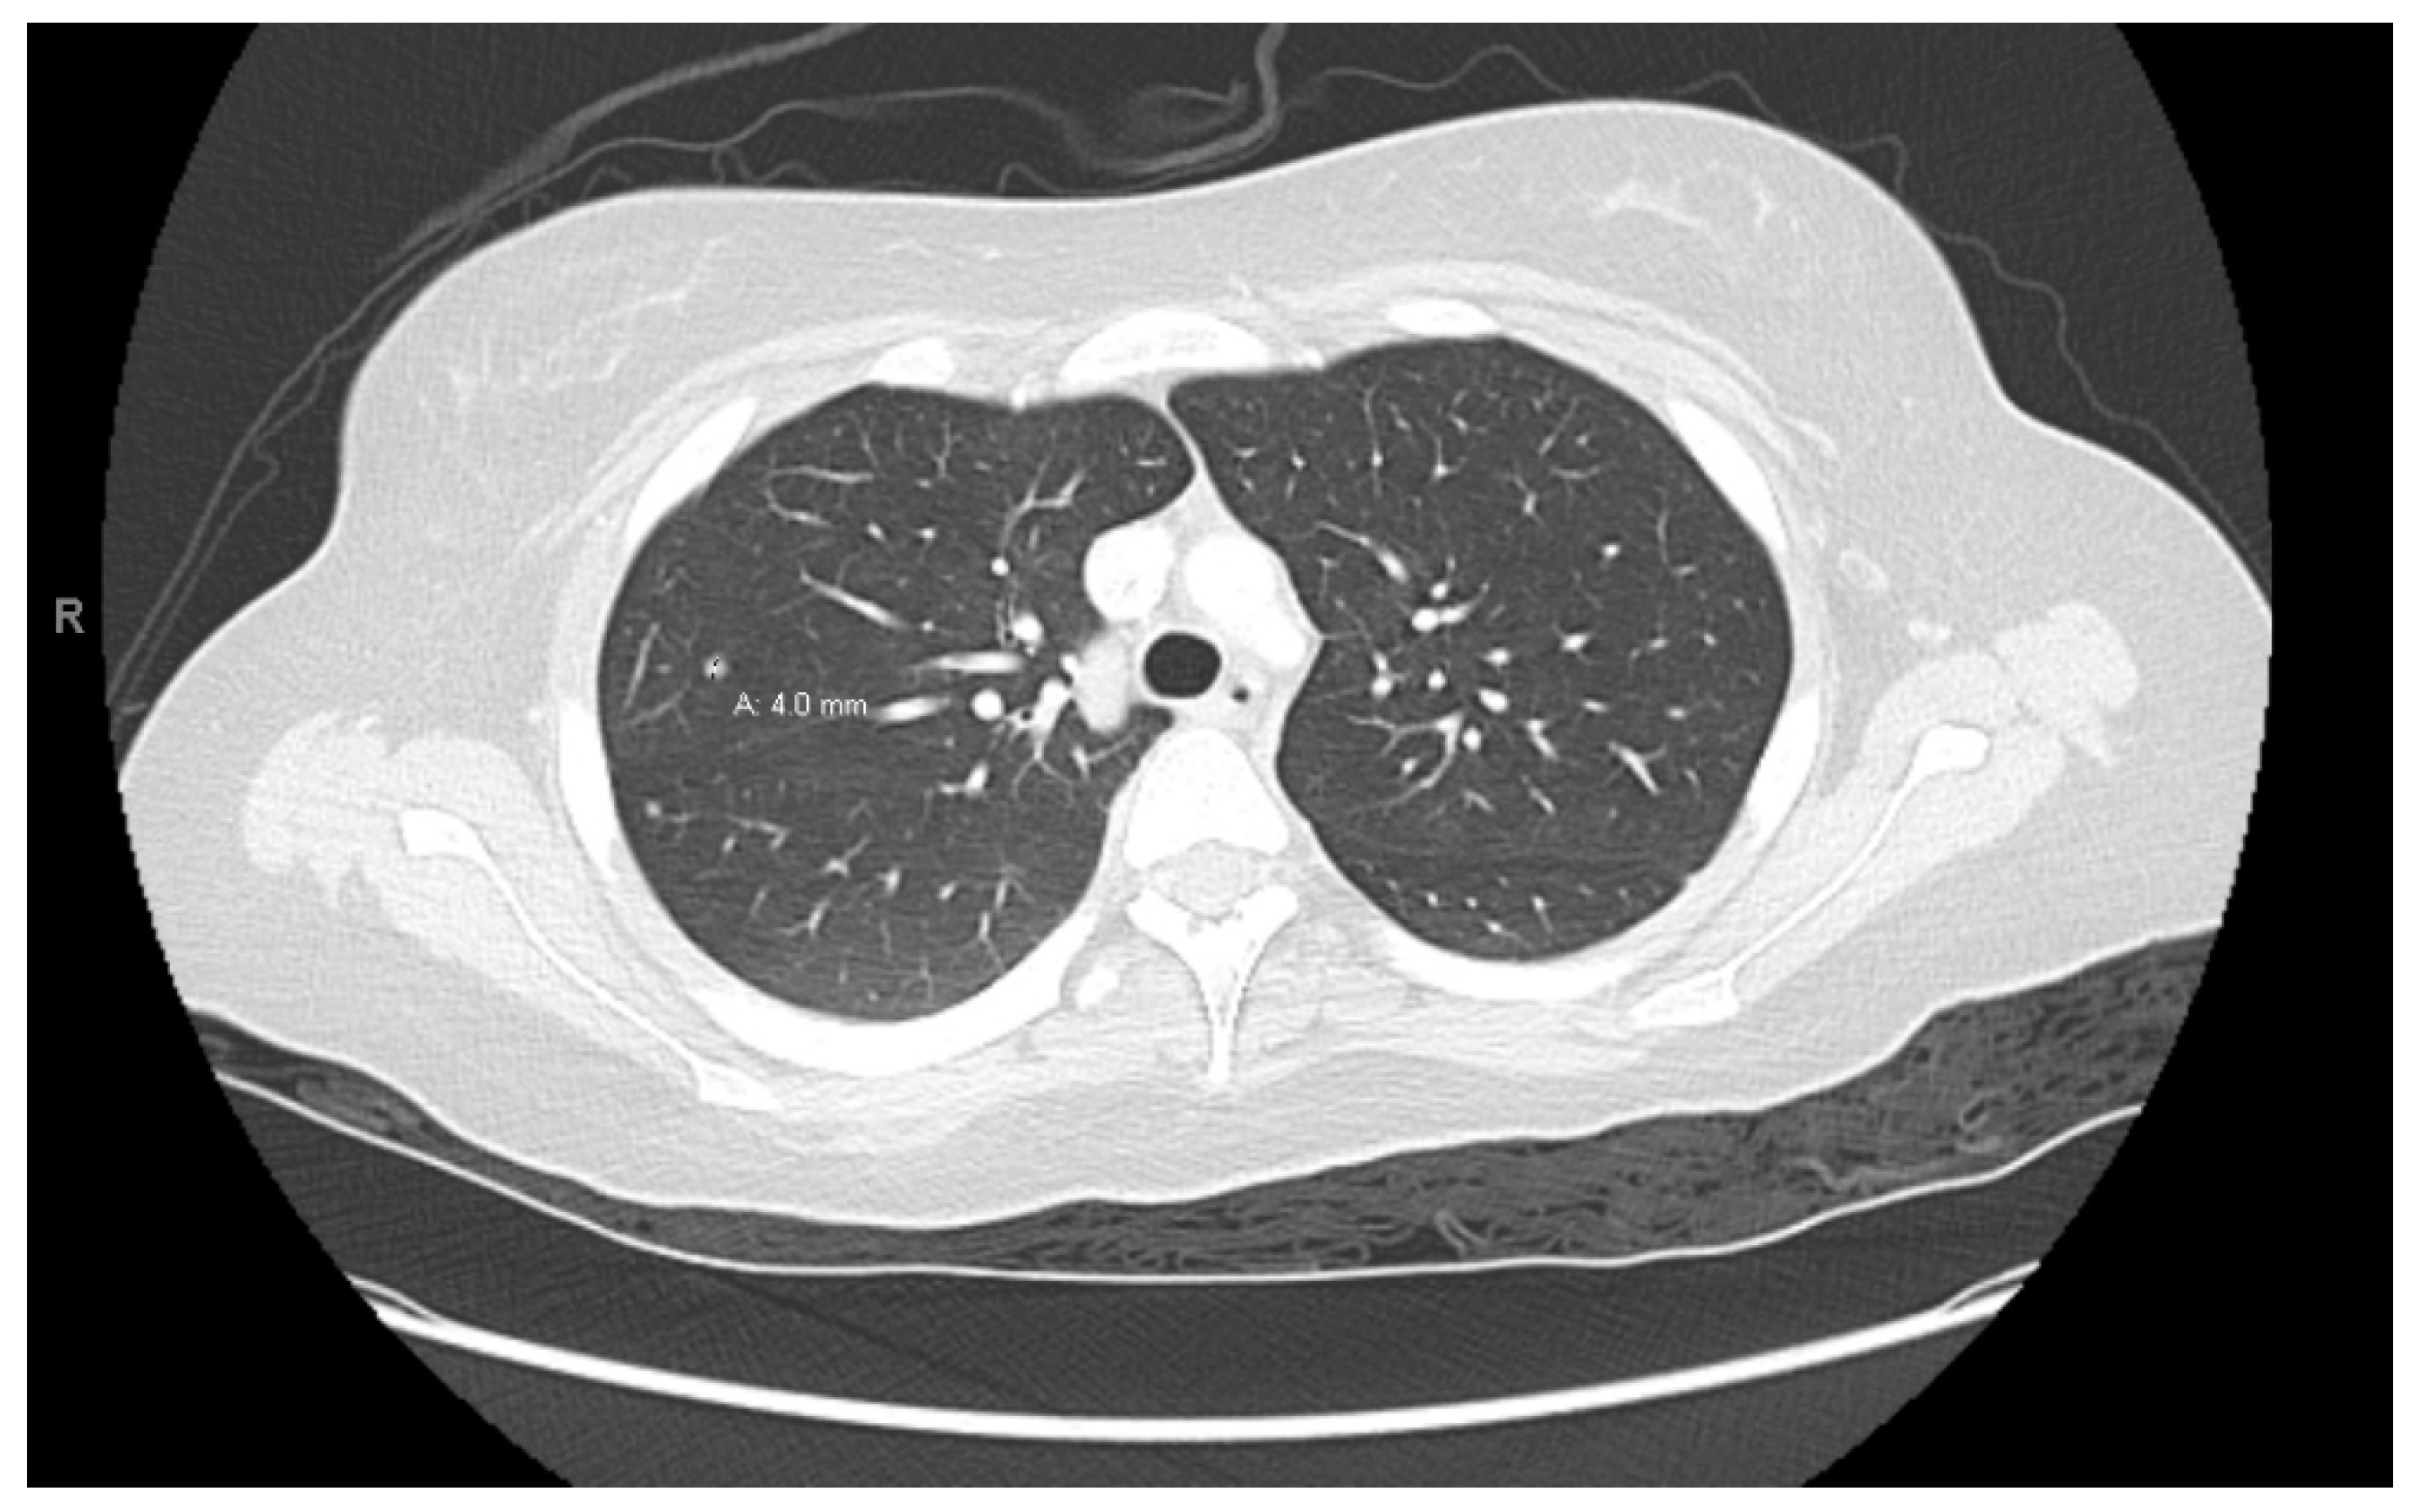

At age 15, she presented to an outside ER with a 2–3-day history of worsening right lower quadrant abdominal pain, nausea and occasional vomiting. She also had a history of a 20-lb weight loss over the past few months due to decreased appetite. CT scan showed a right renal mass 7 cm in size. She was transferred to our hospital and MRI abdomen/pelvis showed an indeterminate left adrenal nodule (Figure 3) and a large, solid, peripherally enhancing right renal mass with central heterogeneity measuring 8.1 × 5.4 × 8.7 cm (Figure 4). It also showed retroperitoneal lymphadenopathy with a retrocaval node at 4.1 × 2 cm, superior retrocaval node at 2.6 × 1.6 cm and an inferior precaval/aortocaval node at 1.5 × 0.9 cm. There was also a right lung nodule noted on a chest CT (Figure 5). She then had a baseline positive emission tomography (PET) scan which again showed the right renal mass, concerning for primary renal cell carcinoma, FDG avid retroperitoneal lymphadenopathy, concerning for metastasis and small bilateral pulmonary nodules, concerning for metastasis. She underwent a biopsy of the right renal mass, which was inconclusive. She underwent a second biopsy and was found to have RCCU-MP manifesting as a high-grade malignancy with loss of SMARCB1 by immunohistochemistry in the absence of a sickle hemoglobinopathy.

Figure 5. Right lung nodule.